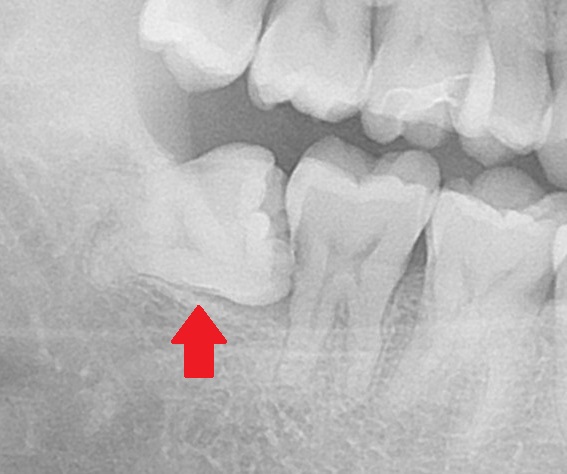

エックス線(レントゲン)写真を見てみると、

親知らずが横向きになっているのが分かります。

そして手前の歯にぶつかっています。

手前の歯に当たっている所が何やら黒くなってるのが分かりますでしょうか?

ここです。

ここが虫歯になっています。

1つ前のレントゲン写真と見比べると、赤枠の部分が黒く映っているのが分かりますね。

お口の中からは見えない部分なのですが、親知らずに物が詰まり、年月が経ち手前の歯を虫歯にしてしまいました。